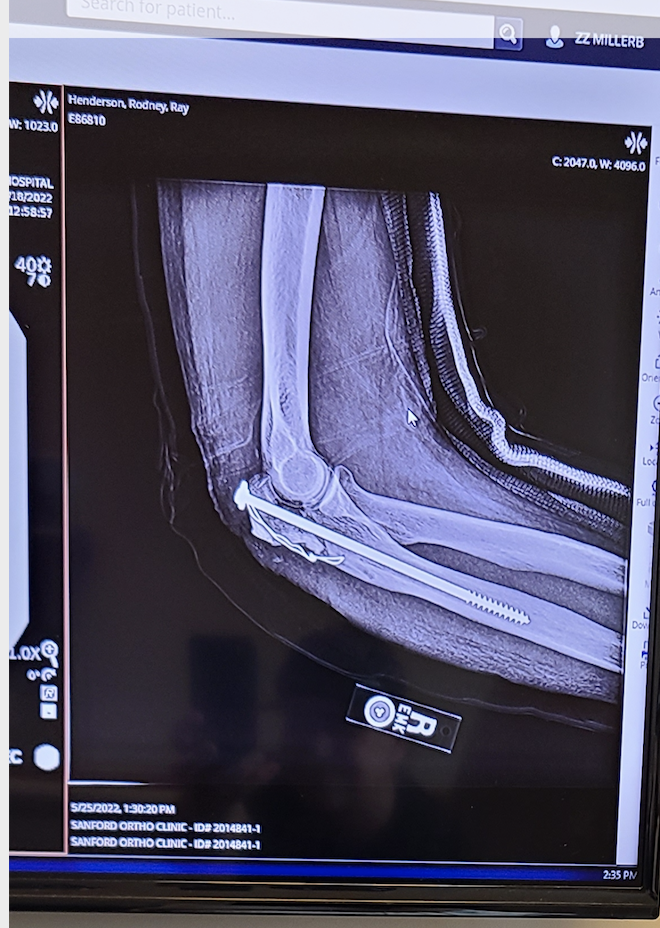

He broke his shoulder and sternum, an elbow and a heel.

“I had to gain range of motion in my right elbow,” he explained. “At first, I did the whirlpool and swimming pool. And then I found the sauna. And I’d sit there for 10 minutes to begin with and straighten my elbow out and bring it all the way back in. And that would help. I just kept doing it, and it got better and better.”

When he went for a checkup a few weeks later, “the doctor was totally impressed,” he said. “They said, ‘I don’t know what you’re doing but keep doing it.’ And I just said I joined Woodlake, and I get in the sauna and stretch it and do some floating around and swimming, and he thought it was amazing. He couldn’t believe how fast it came around.”